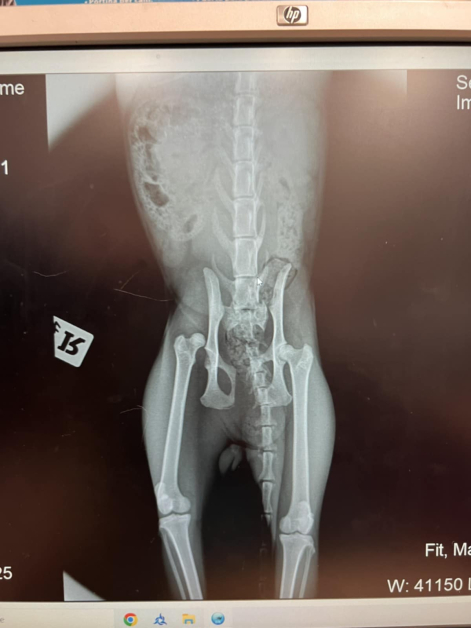

Жената незабавно вади клетото животинче и се свързва с доброволец от фондация, помагаща на животни в неволя. Котенцето е откарано при ветеринар, където се оказва,че има строшаване на таза и от двете страни.

" Рижко ще живее, няма наранени нерви на гръбнака, само че му предстоят нелеки интервенции по слагане на пластини. Настанен е в клиника в Пловдив и ще разчита на благотворителността на положителни хора, с цел да се събере сумата за интервенциите ", пишат до медията ни доброволци.

Докторите са безапелационни, че през задната му част е предходна кола. В момента е на обезболяващи лекарства и още през днешния ден може ще бъде опериран.